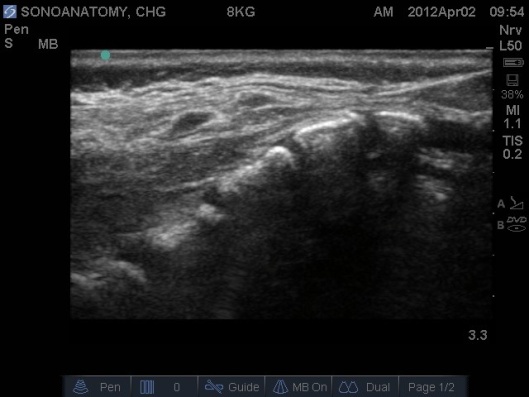

- Prior to performing the caudal a ‘Mapping’ or ‘Scout’ scan is performed to assess the position of the dural sac in relation to the sacrococcygeal membrane. The angle of needle/cannula insertion can be observed. See Figs 1-7.

- The probe should be placed in a transverse plane over the sacral hiatus first, then rotate the probe into a midline sagittal plane (the left of the screen should be cephalad).

- The author’s preferred technique is to insert the cannula at the very apex of the sacral hiatus perpendicular to the skin. Once resistance is felt re-angle the needle to approx. 30 degrees and insert a further 5mm, then slide the cannula off the needle (it should slide off easily).